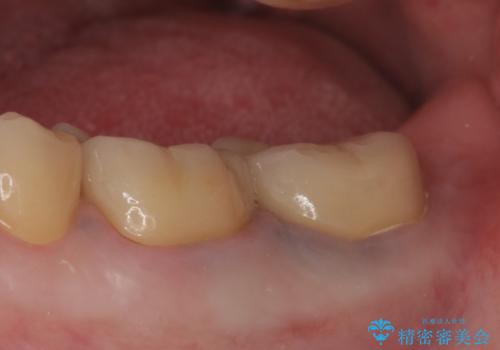

症状の消失を確認後、オールセラミッククラウンによる補綴を行いました。

今回用いたオールセラミッククラウンは、ジルコニアフレームという白い素材の上にセラミックを盛っているため審美性が非常に高いのが特徴です。

またジルコニアは人工ダイヤモンドの材料にも使われているほど高い強度を持っており、そのためオールセラミッククラウンは審美性だけでなく、奥歯やブリッジの補綴も可能とするクラウンです。